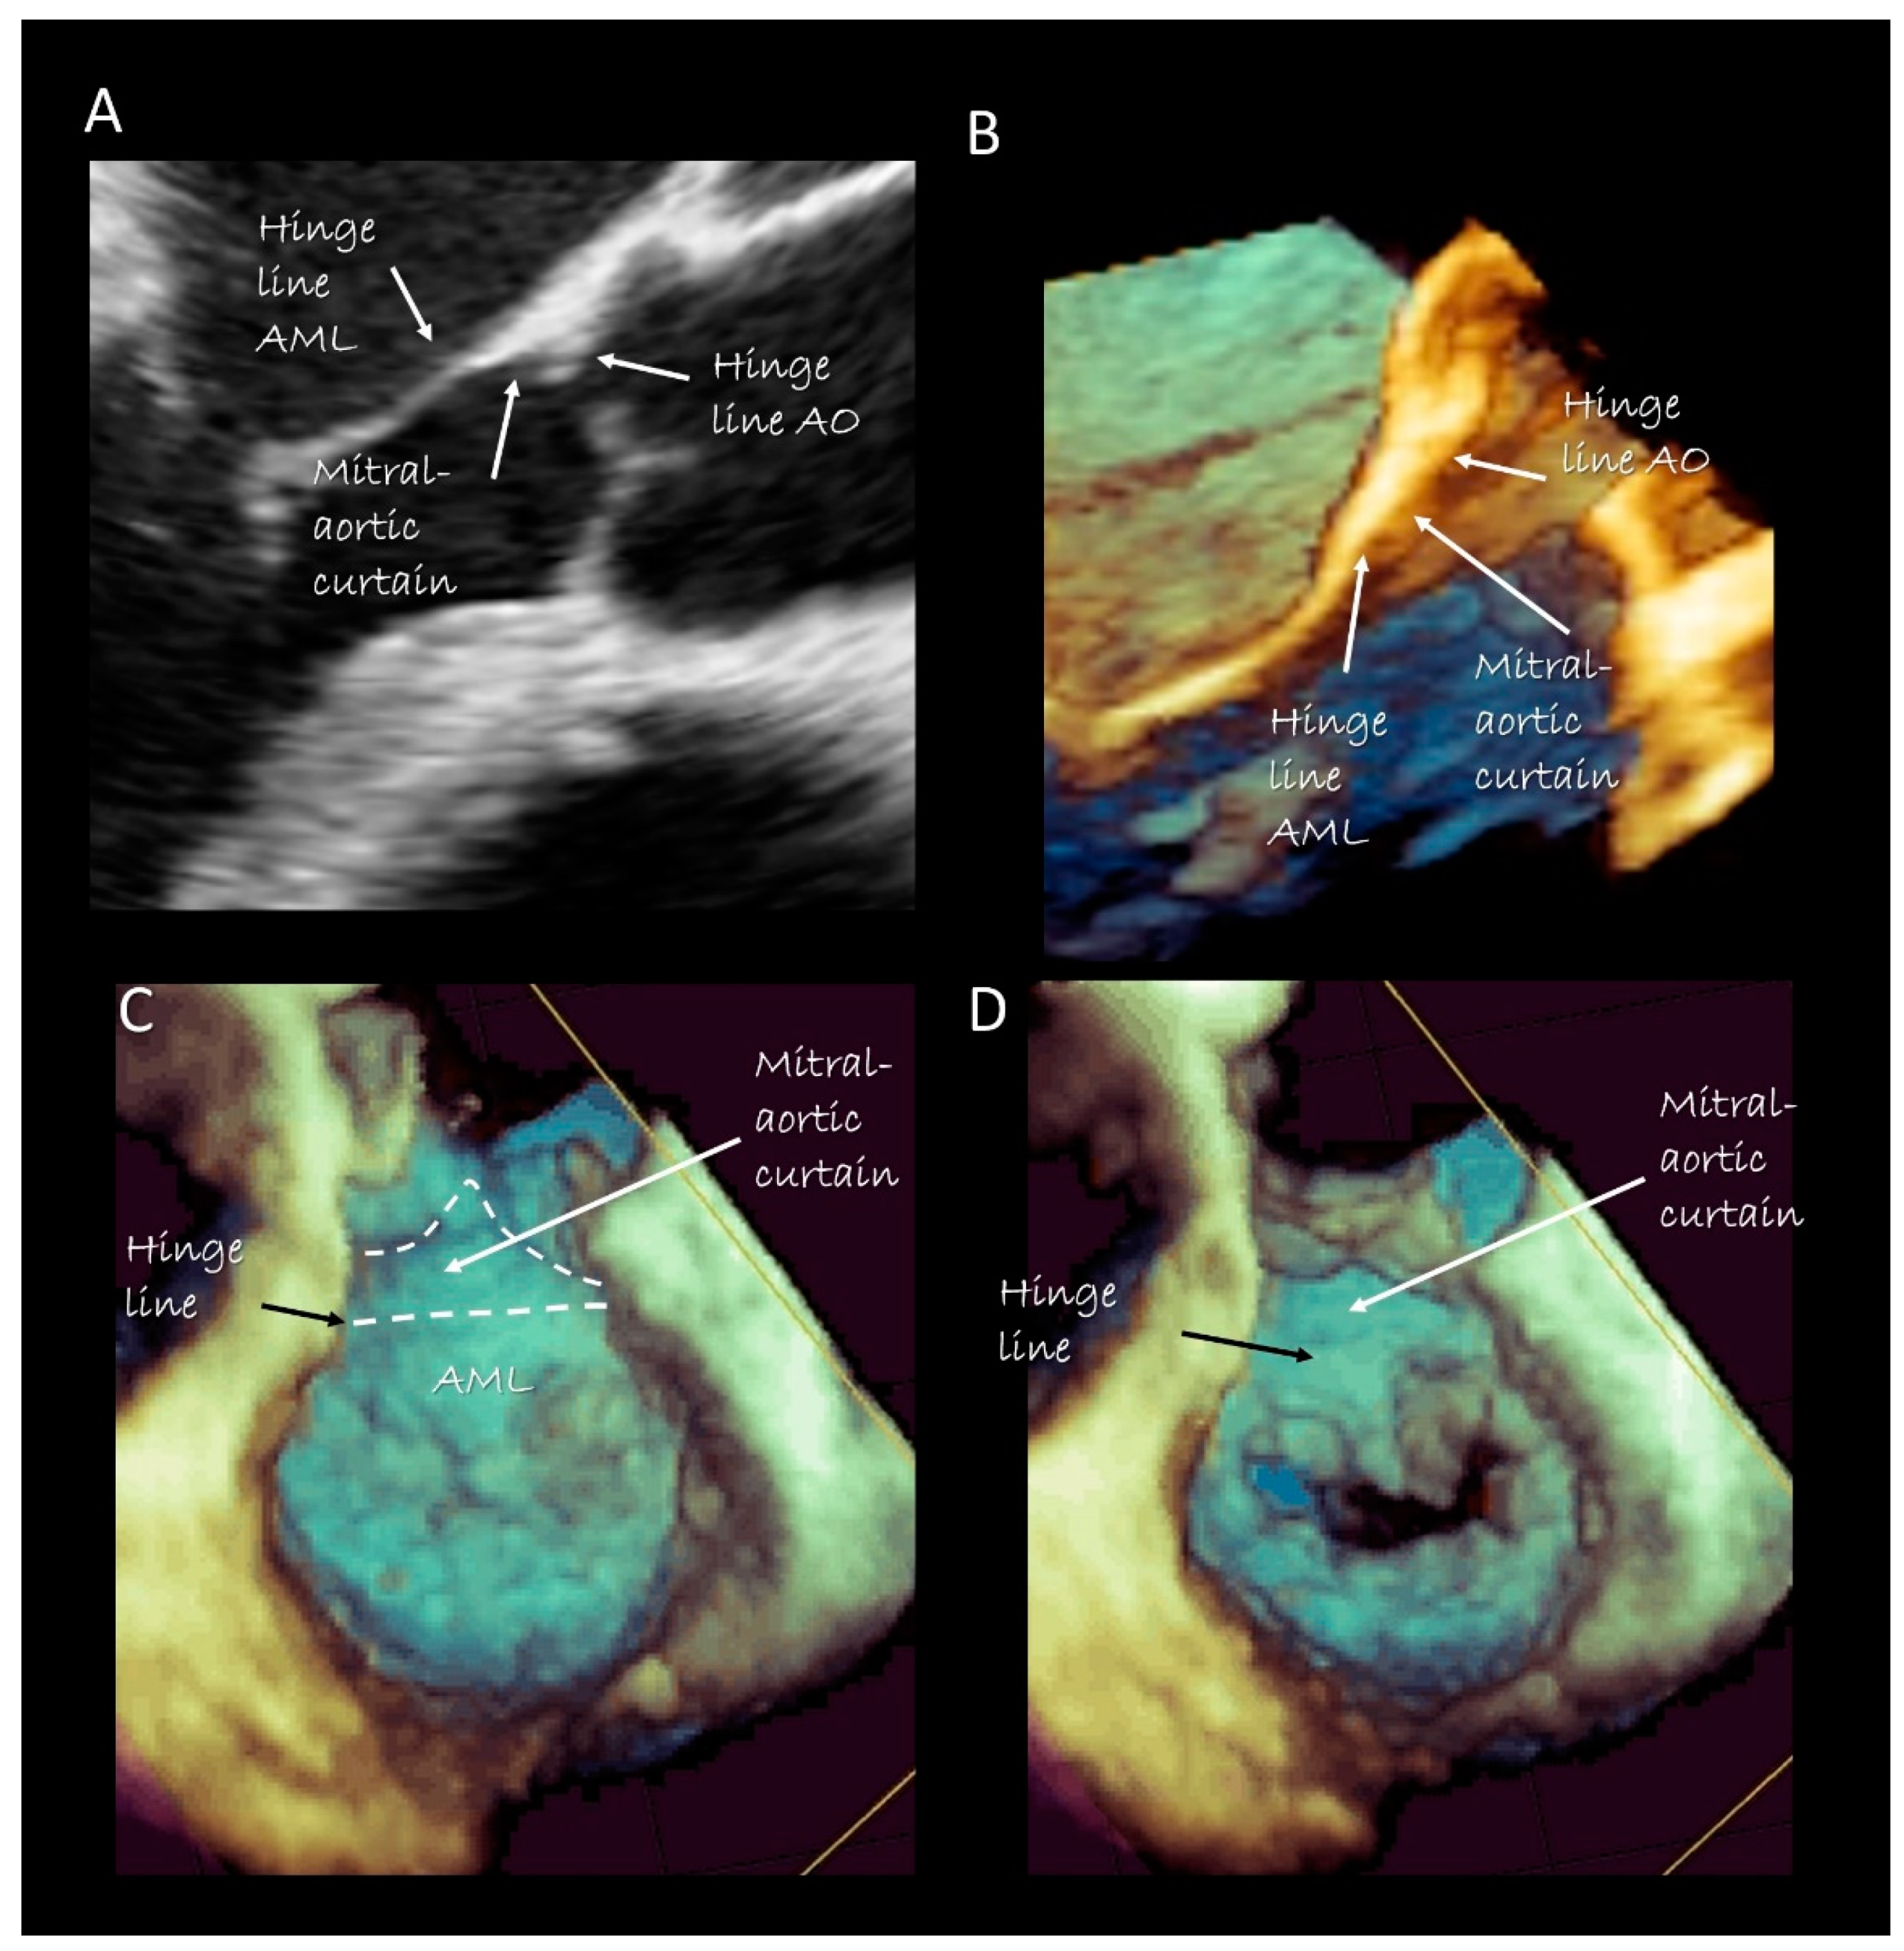

3. Mitral Leaflets

Imaging Techniques

7. Surgical and Interventional Implications